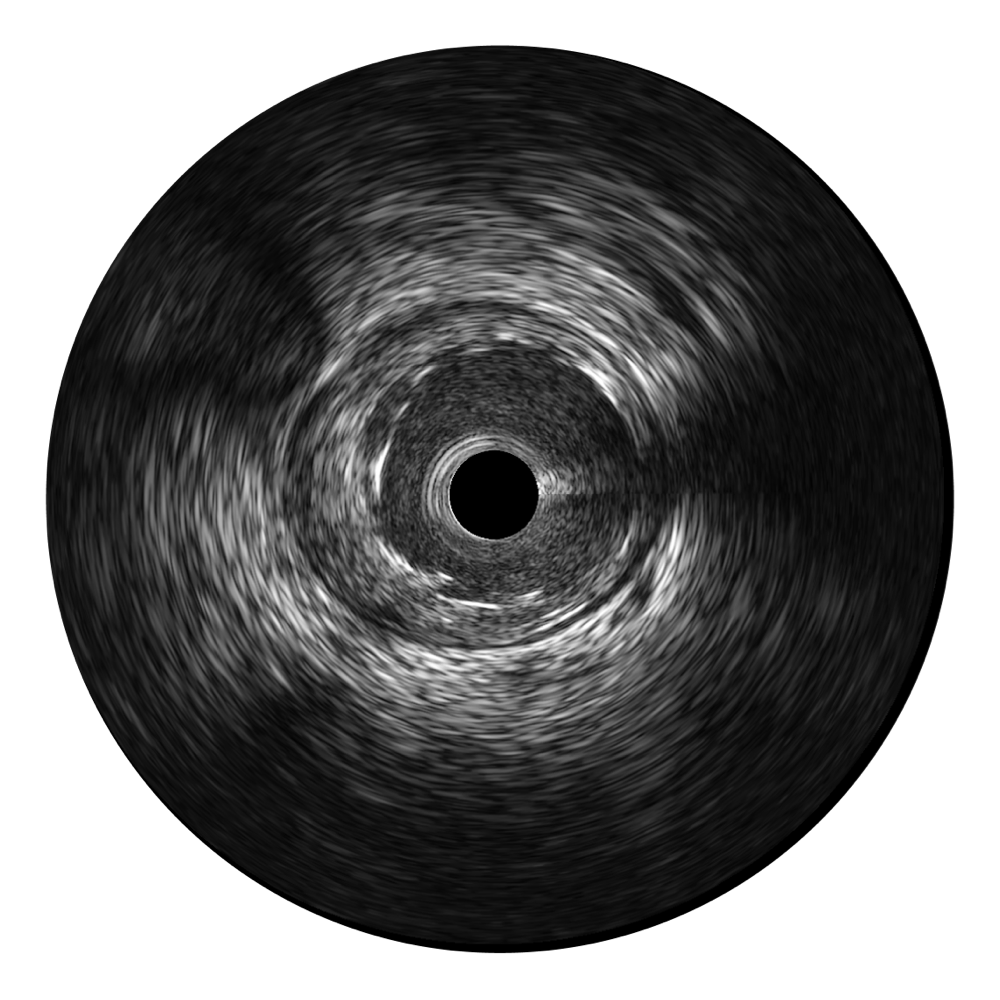

单晶超宽频IVUS VS 传统陶瓷材料IVUS

乐玩lewin国际超宽频成像技术覆盖20-80MHz1或20-90MHz2频率范围, 提供优异的分辨力同时也保证充足的穿透深度